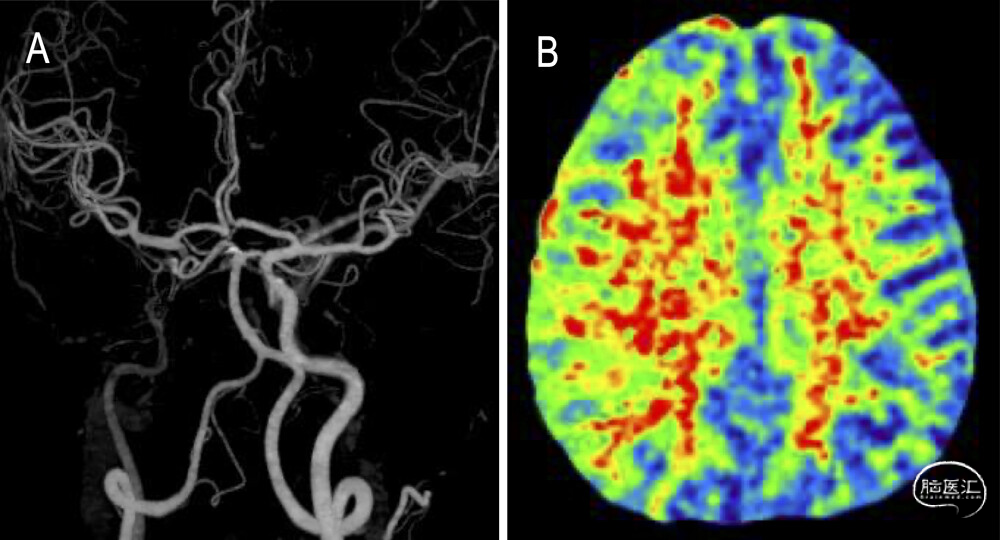

● CT检查可见蝶窦占位,右侧海绵窦、鞍底及斜坡存在溶骨性改变(图1A);MRI检查见一直径39毫米的肿物充满蝶窦,与鞍底边界不清,稳态构成干扰序列显示病变向右侧动眼神经池延伸(图1B),并将正常垂体向上推移,病变信号不均,呈高信号与等信号混杂(图1C、D),提示出血或富含蛋白成分,无强化表现(图1E);MR血管成像显示右侧颈内动脉轻度狭窄(图1F),弥散加权成像未见缺血灶。尽管患者无相关缺血症状,但4天后复查MR血管成像显示狭窄显著加重,近乎闭塞(图1G),CT灌注血管成像证实右侧颈内动脉重度狭窄(图2A),尽管右侧颈内动脉存在狭窄,但右侧大脑中动脉供血区脑血流量、脑血容量未下降,然而平均通过时间与达峰时间延长,提示广泛灌注延迟(图2B)。除视神经、动眼神经症状快速进展外,患者还出现颈内动脉急性近乎闭塞伴脑灌注不足,因此紧急实施手术干预。

图2:A:CT灌注血管成像示右侧颈内动脉显影不佳。B:术前CT灌注成像示平均通过时间(MTT)提示右侧大脑半球灌注延迟。